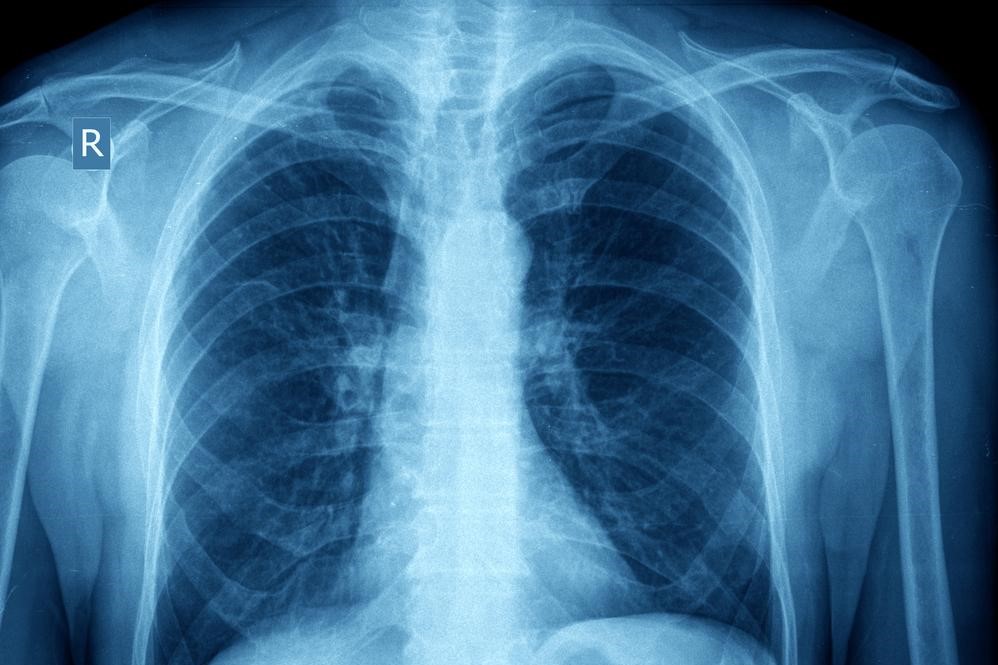

Pathology and Pathophysiology of Asthma

Asthma takes place in two forms; acute and chronic. Acute asthma, known as an asthma attack is an episodic event that occurs due to an asthma trigger. Chronic asthma develops due to the changes that occur from prolonged inflammation over time.

It is believed that patients always have some degree of inflammation in the lungs that make them more sensitive triggers. Chronic inflammation over time can lead to changes in the structures of the lungs and increased mucous production. Proper control of asthma can limit these effects.